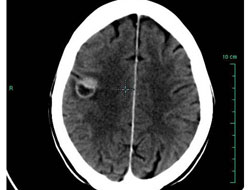

Radyoterapi ve kemoterapideki ilerlemelere rağmen beyin tümörü türlerinin en sık rastlanan ve en tehlikelisi olan glioblastoma tümörü hastalarının yüzde 50'si teşhisin konulmasından sonra 1 yıl içinde yaşamını yitiriyor.